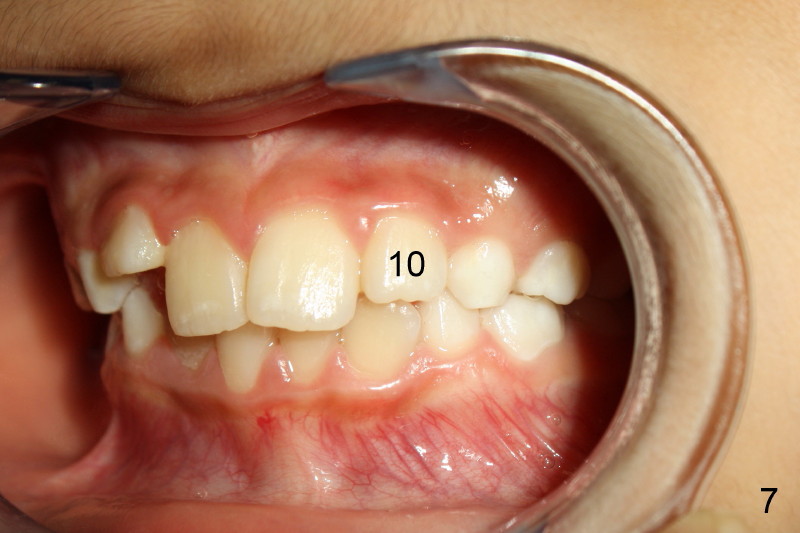

Panramic X-ray was taken when Edward was 6 years 5 months old (Fig.1). His parents and he himself found that the upper right lateral did not erupt at the age of 9 years 2 months (Fig.2-4: *). Gingivectomy was performed using soft tissue laser to expose the incisal edge of the lateral. Five months later, the lateral has erupted partially (Fig.5-8), but the family is concerned about the cosmetic issue. It appears that the upper midline has shifted to the right (Fig.6). Periapical film is planned to take to confirm the relationship between the canine and the lateral.

Appears that #7 is short a little room, therefore mechanically obstructed. Solution: make room! How? Slenderize the adjacent primary canine, extract C and H, or mild expansion. Tim Shaughnessy, DDS 11/22/2012